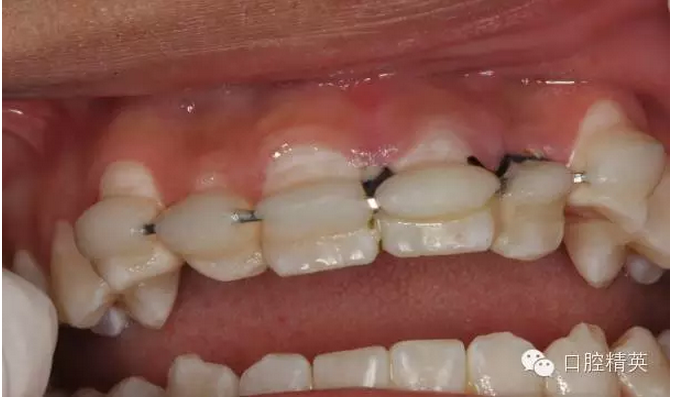

術(shù)后一周患者復(fù)診情況及術(shù)后一個(gè)月復(fù)診情況報(bào)道給大家:

圖1.一周后復(fù)診拆線(xiàn)、唇側(cè)齦乳頭水腫。

圖2.拆線(xiàn)前腭側(cè)觀

圖3.拆線(xiàn)后唇側(cè)觀,牙齦乳頭輕度水腫

圖4.腭側(cè)觀21齦乳頭水腫明顯